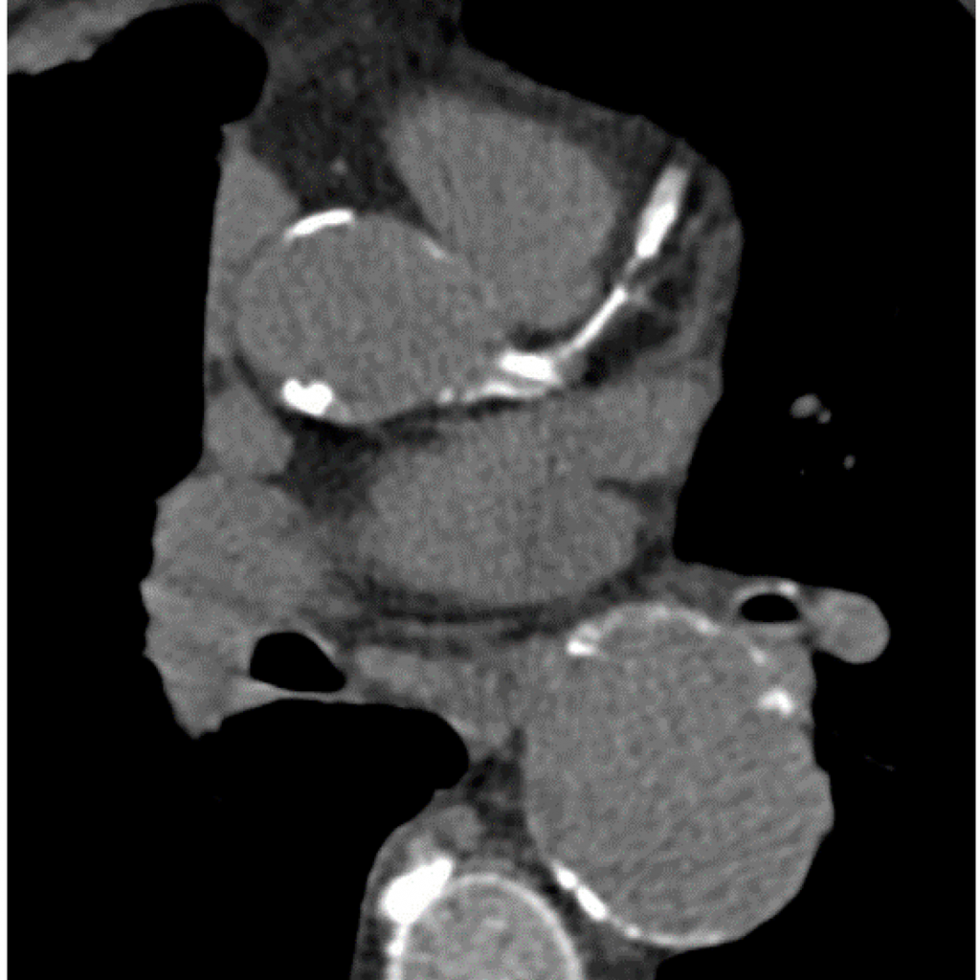

What is CT Angiography (CTA)?

skull x-ray

CT angiography uses X-rays to view blood flow in blood vessels throughout the body, from arteries serving the brain to those bringing blood to the lungs, kidneys, arms, and legs. Beams of X-rays create cross-sectional images that are assembled by a computer into a three-dimensional picture of the area in question.

Why might my doctor recommend CT Angiography (CTA)?

A CTA may be recommended for a variety of reasons. CTA helps visualize blood flow in the arteries that serve your kidneys, in patients with high blood pressure and those who are suspected of having kidney disorders. It also is used to identify life threatening aneurysms in heart and brain. CTA also can help detect narrowing and blockage in the arteries.